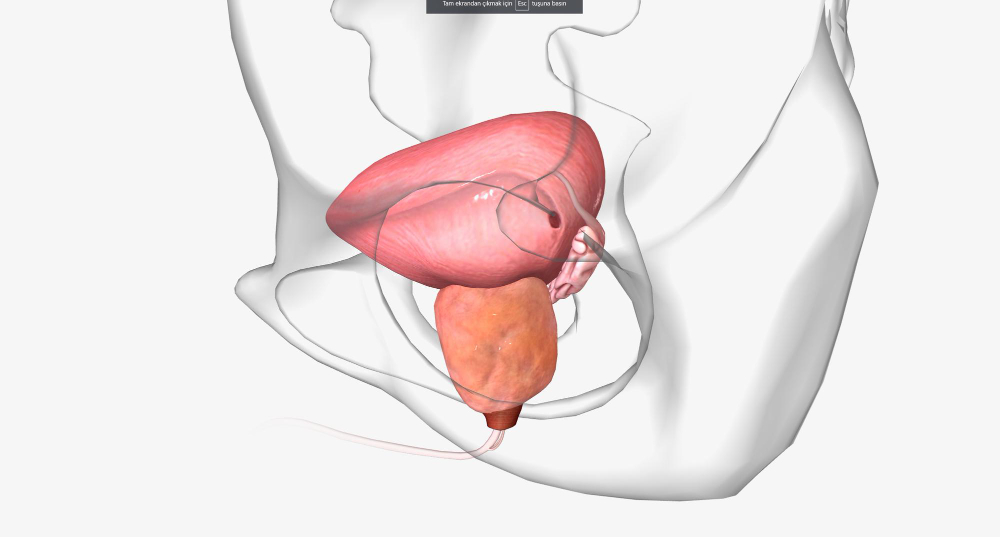

הערמונית, מזכירה בצורתה את הערמון מכאן שמה בעברית, ממוקמת מתחת לשלפוחית השתן וסובבת את השופכה, אשר עוברת דרכה. לכן, כאשר הערמונית גדלה – היא עלולה ללחוץ על השופכה ולגרום לקשיים בהתרוקנות, זרם שתן חלש, לצורך תכוף במתן שתן, להטלת שתן לילית, ומאידך אף לעצירת שתן מוחלטת או לזיהומים חוזרים. אמנם מדובר בבעיה שאינה מסכנת חיים, אך היא עשויה להשפיע רבות על התפקוד היומיומי, על איכות השינה, ועל איכות החיים האישית של המטופל.

בלוטת הערמונית ממוקמת כאמור מתחת לשלפוחית השתן והשופכה עוברת דרך בלוטה זו. במהלך החיים, במיוחד מגיל 50 ואילך, הערמונית נוטה לגדול. מדובר בתהליך טבעי הקשור לשינויים הורמונליים – בעיקר ברמות הטסטוסטרון והדיהידרוטסטוסטרון (DHT). ההגדלה גורמת ללחץ על השופכה ולפגיעה בזרימת השתן. מדובר בבעיה שאינה ממארת, אך בעלת השפעה ניכרת על איכות החיים. נתונים עדכניים מצביעים על כך שכ־50% מהגברים בגיל 60 סובלים מהגדלה שפירה של הערמונית, ובגיל 80 – למעלה מ־80% מהגברים מושפעים ממנה.